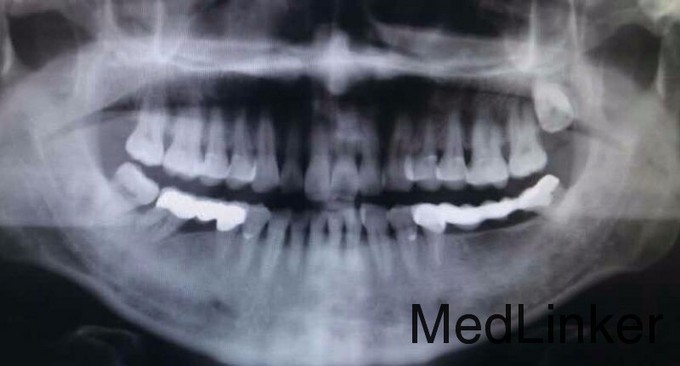

1107低位垂直阻生智齿的拔除光9

最近一周左上后牙不适,要求拔除

垂直阻生齿

垂直阻生